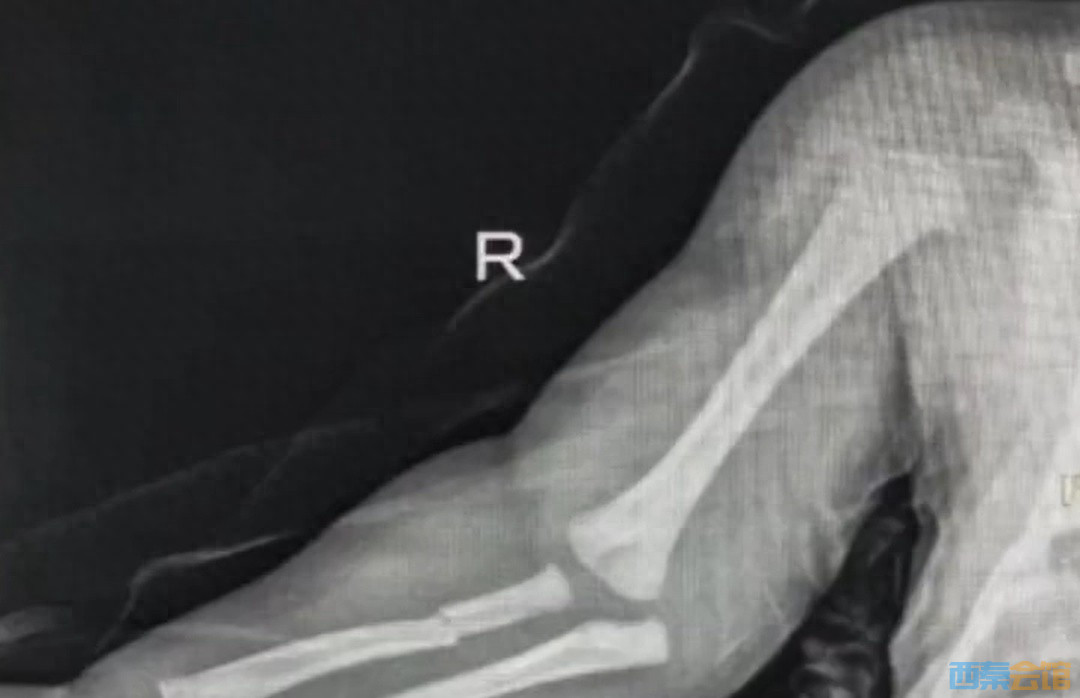

广州一15天大婴儿双上肢多处骨折,医院回应:婴儿系坠床导致骨..

1小时前你最好别惹我